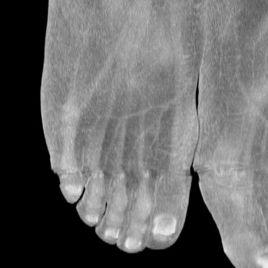

偽影(Artifacts)是指原本被掃描物體並不存在而在圖像上卻出現的各種形態的影像。偽影大致分為與患者有關和與機器有關的兩類。

漢字釋義 物理學 地球-太陽 月球-太陽 虛擬人物靜電偽影磁共振成像術語。 ?磁共振成像偽影之一。 由於病人的尼龍衣褲、尼龍襪以及有些毛毯產生靜電,干擾了MR信號產生的偽影。